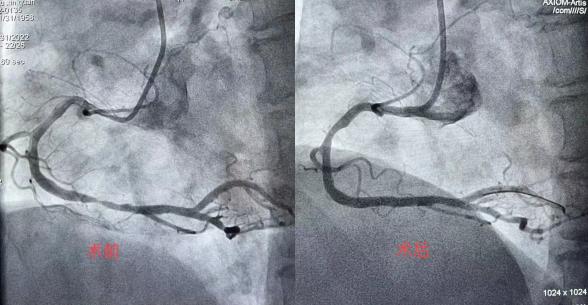

作为国家级胸痛中心,沈医二院·退役军总拥有一整套能让患者在黄金救治时间内被抢救、得到有效治疗的绿色通道。秉承“时间就是心肌”的救治理念,急诊室迅速联系心血管四科会诊,第一时间为朱女士开启胸痛中心绿色通道。心血管四科邵冰主任认为,患者存在急诊进行冠脉介入手术治疗的指征。冠脉造影结果也显示,朱女士的冠脉存在多支血管病变,右冠严重狭窄,病变密度浅淡。姚敏医生与介入手术室的相关人员火速到位。患者病情十分不稳定,曾出现血压下降。邵冰主任沉着应对,凭借高超的手术技巧、过硬的心理素质,予患者及时开通罪犯血管,于右冠植入一枚支架。患者转危为安,生命体征平稳。